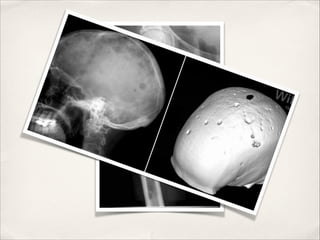

Imágenes: radiografías simples, resonancia nuclear magnética si la

En el estudio siguiente presenta creatinina 0.6 mg/dL, calcio 8.9 mg/dL,

hematocrito 42%, proteinuria de Bence Jones y determinación de cadenas livianas

negativas. Radiografía de cráneo y huesos largos normales.!

Paciente de 70 años, sin antecedentes mórbidos, sufre fractura de tercio medio de

fémur derecho. Intraoperatoriamente se pesquisa masa friable en el sitio de la

fractura. Biopsia rápida demuestra tumor de células plasmáticas.

negativas. Radiografía de cráneo y huesos largos normales, electroforesis de

proteínas séricas y de orina normales.!

!

Mielograma y biopsia de médula ósea normales.